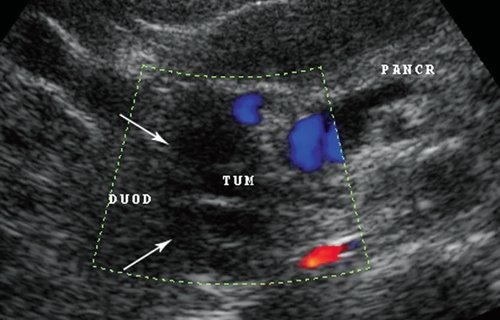

В 1 наблюдении был выявлен атипичный случай дуоденальной дистрофии. При УЗИ диагностировали утолщение стенки двенадцатиперстной кишки, в толще которой визуализировалось образование с достаточно четкими ровными контурами, по структуре анэхогенное, неоднородное, с наличием тонких изоэхогенных перегородок. В режиме цветового допплеровского картирования и энергии отраженного допплеровского сигнала данных о наличии кровотока в перегородках не было получено. В поджелудочной железе были поражены только зоны крючковидного отростка и нижней части головки железы (рис. 8), отсутствовали изменения вирсунгова протока, тела, хвоста и части головки поджелудочной железы, а также признаки билиарной гипертензии. Это заставляет думать либо о выраженной изолированной дуоденальной дистрофии с атрофией крючковидного отростка, либо о блокаде эктопированной тканью аномального протока крючковидного отростка в стенке двенадцатиперстной кишки.

Рис. 8. Изображение кистозного образования (TUM, указано стрелками) в стенке двенадцатиперстной кишки (DUOD) на фоне неизмененной паренхимы поджелудочной железы (PANCR), за исключением крючковидного отростка, в режиме цветового допплеровского картирования.